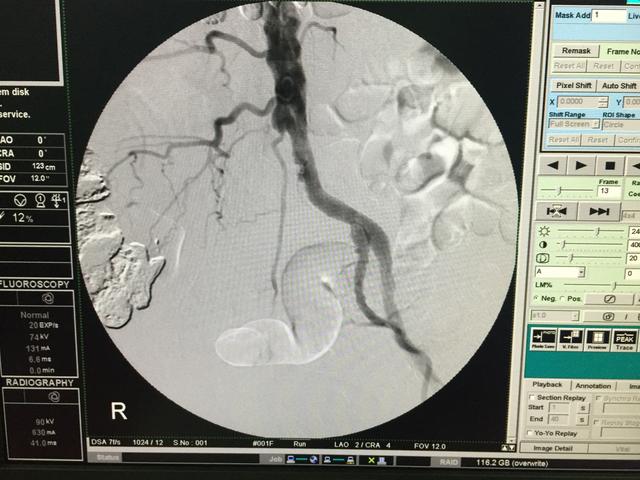

血管外科经常收治一些病人是因为“肾虚”而来的,他们的主要表现是:腰酸腿痛、下肢发凉伴乏力、臀部麻木、性功能障碍等等。这些表现显然符合中医的肾虚,在临床上更容易与腰椎病、偏瘫、髂关节及膝关节病鉴别不清,由于血管病变多见于中老年,与上述疾病发病年龄相当,而且往往会同时伴发,导致长期误诊。

对于这些患者,尤其是孤立的下半身症状患者,一定要注意下肢股动脉、腘动脉、足背及胫后动脉搏动的情况。其次注意温度、皮毛脱落、肌肉萎缩等,另外,还要注意与运动的关系,血管病变类似于心绞痛,活动后出现困痛。

血管外科经常收治一些病人是因为“肾虚”而来的,他们的主要表现是:腰酸腿痛、下肢发凉伴乏力、臀部麻木、性功能障碍等等。这些表现显然符合中医的肾虚,在临床上更容易与腰椎病、偏瘫、髂关节及膝关节病鉴别不清,由于血管病变多见于中老年,与上述疾病发病年龄相当,而且往往会同时伴发,导致长期误诊。

对于这些患者,尤其是孤立的下半身症状患者,一定要注意下肢股动脉、腘动脉、足背及胫后动脉搏动的情况。其次注意温度、皮毛脱落、肌肉萎缩等,另外,还要注意与运动的关系,血管病变类似于心绞痛,活动后出现困痛。